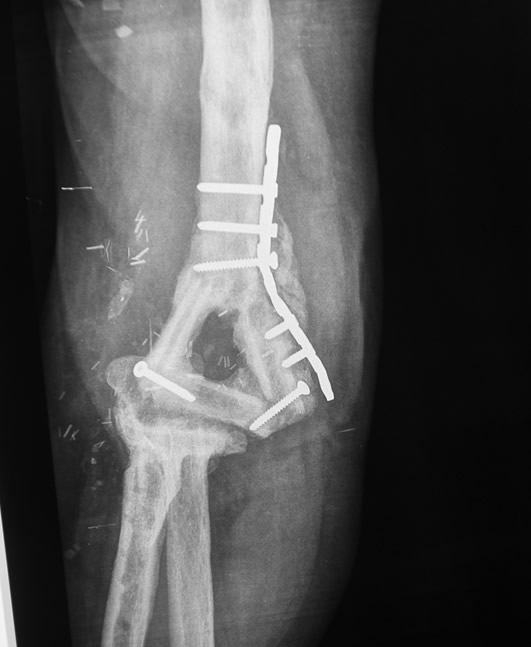

Paso 1: Reconstrucción extremo distal de codo con hueso vascularizado

Transferencia de hueso vascularizado de cresta ilíaca tallado a la forma de cúbito proximal.

Paso 2: Reconstrucción de extremo proximal codo con hueso vascularizado

Reconstrucción de húmero distal con transferencia microvascular de peroné tallado.

Paso 3: Reconstrucción de ligamentos

Reconstrucción de ligamentos laterales de codo con injertos tendinosos.

03. Resultado

El resultado funcional fue excelente con movilidad y estabilidad normales del codo y ausencia de dolor.

- Reconstrucción totalmente autóloga (tejido propio)

- Función casi normal e indolora del codo reconstruido